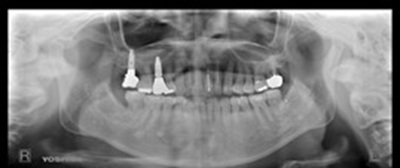

術後の状態

術後パノラマ

奥の歯(7本目)― Zimmer社製スプラインを使用

この部位では、骨がやわらかく初期の安定が得にくいことから、Zimmer社のスプラインインプラントを採用しました。このタイプはねじ山が深く、柔らかい骨でもしっかりと固定される構造になっています。骨の高さを補うためにソケットリフトを行い、骨補填材を併用して安定した支えを作りました。手術後も動揺や骨吸収は見られず、長期的に安定した状態を保っています。

手前の歯(5本目)― Straumann社製ボーンレベルSLActiveを使用

手前の歯では、抜歯と同時にインプラントを埋め込む「抜歯即時埋入」を行いました。この部位では骨はしっかりしていましたが、噛む力が強く、歯ぎしりの影響を受けやすいため、高い精度で補綴物と連結でき、咬合力に強い構造を持つStraumann社のボーンレベルSLActiveを選択しました。このインプラントは表面が特殊に処理されており、骨との結合が非常に速く進む特徴があります。

埋入後4か月で最終的な被せ物を装着しました。咬み合わせを調整し、ナイトガードを使用して就寝時の負荷を軽減しました。現在も4か月ごとのメインテナンスを継続しており、インプラントと周囲の歯ぐきは安定しています。骨質や噛む力、部位ごとの条件に合わせてインプラントを使い分けることが、長く良い状態を保つために大切だと改めて感じました。